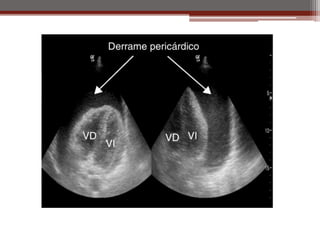

c) Derrame pericárdico • Mayor a 50 ml de líquido

• Disminución de los ruidos

• Síntomas:

▫ Cantidad de líquido

acumulado

▫ Velocidad de acumulación

• Taponamiento cardiaco

Ecocardiograma

1. Estudio más eficaz para

derrame pericárdico

2. Permite identificar

cardiomegalia por

dilatación de cavidades

o derrame pericárdico.

3. Cantidad de derrame